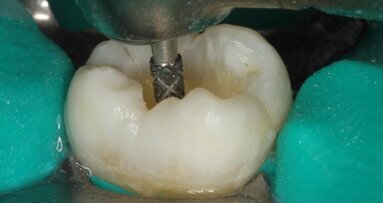

In order to obtain a favourable result in a relatively short time, the patient preferred a combination of home and power whitening. An alginate impression was taken prior to the first in-office whitening session (Fig. 3). While the patient received whitening of the upper arch for 40 minutes, a model was poured and a customised tray was fabricated. Thus, it was possible to deliver the upper tray and the home whitening kit on the day of treatment.